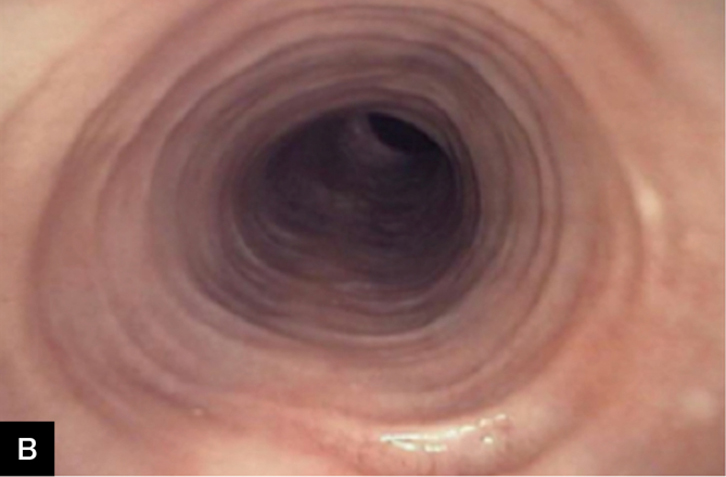

• Colonoscopy